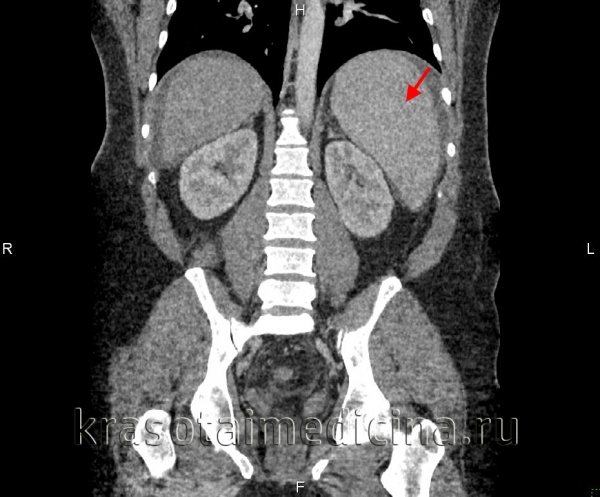

КТ ОБП. Диффузное увеличение печени (зеленая стрелка) и более выраженное увеличение селезенки (красная стрелка).